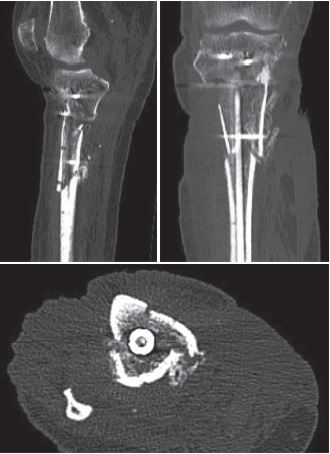

Three months following the injury it was determined that the diaphyseal component had no significant union or callus. The patient underwent removal of all of the infected metal. Extensive purulence was noted in the medullary cavity throughout the metaphysis. The non-union sites were aggressively debrided to bleeding healthy bone (Figure 6). The tibial canal was then reamed to prepare for a tibial nail using an infrapatellar approach so as to avoid inoculating the knee joint with infected debris. An injectable antibiotic loaded bio-composite (Cerament V and G — containing vancomycin and gentamicin) were then inserted through the non-union sites into the canal followed by an intramedullary nail (Figure 7). A blocking screw was used to address the procurvatum deformity in the sagittal plane. A medial gastrocnemius flap and skin grafting was then performed by plastic surgeons. Samples from this surgery grew methiillin resistant Staphylococcus Aureus (MRSA), Pseudomonas Aeruginosa, Candida Parapsilosis, Enterococcus Faecium and Staphylococcus Haemolyticus. Of these samples the dominant growths were Pseudomonas (sensitive to Gentamincin), Candida (sensitive to fluconazole) and MRSA (sensitive to linezolid). Post-operative antimicrobial treatment included ceftazidime, linezolid, ciprofloxacin and fluconazole.

Figure 6. Intra-operative images demonstrating infected non-union sites at 3 months

Figure 7. Plain X-rays after removal of dual plate fixation. Cerament V was inserted into canal and then intramedullary tibial nail was inserted

After a period of three months, the patient’s antibiotics have been discontinued, however he remains on Fluconazole for at least another 6 months. Despite these challenges, the patient currently shows signs of recovery, mobilizing over short distances, weight-bearing with assistive aids and with healing wounds and early signs of callus formation on recent CT scans and plain X-rays (Figure 8, 9, 10). His inflammatory markers have improved significantly with a latest C-reactive protein of 14.7 from 250 mg previously (reference range 0-5) and normal white cell and neutrophils count.

Figure 8. Plain X-rays 3 months after removal of dual plate fixation with insertion of cerement V and intramedullary nail showing satisfactory alignment and early callus formation

Figure 10. Sagittal, coronal and axial CT images displaying callus formation at fracture site at 3 months post-operatively